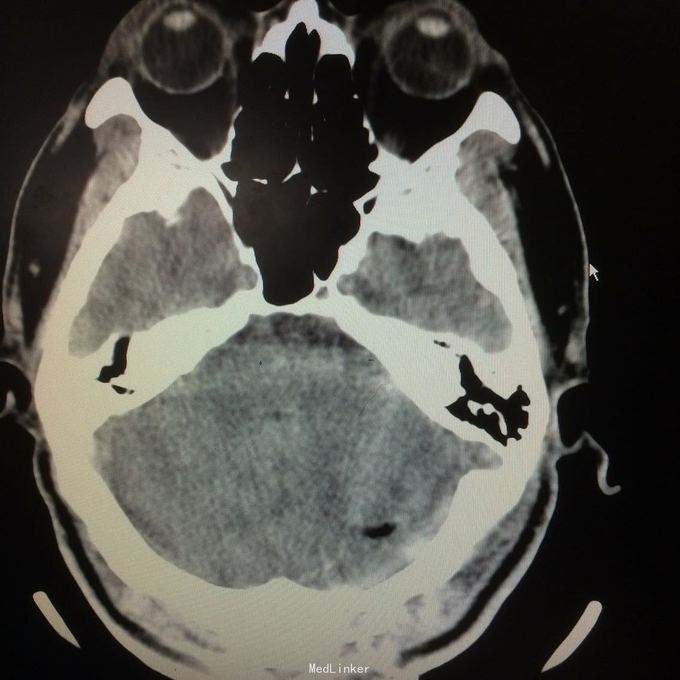

主诉:头晕头痛2年 病史:2年前无明显诱因出现头痛,呈刺痛,程度较重,伴头晕、天旋地转感,1年前查头颅MR提示:左侧小脑半数囊性病变,考虑血管母细胞瘤

查体:神志清楚,病理证阴性 辅助检查:头颅MR提示左侧小脑半数后部囊状占位灶,考虑良性病变。

诊断:左侧小脑血管母细胞瘤 处理:行左侧小脑占位病变切除术,术后病理提示:符合血管母细胞瘤。